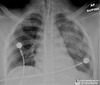

CXR: ARDS, exclude perforated DU

Respiratory: ARDS, pleural effusion